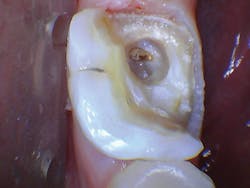

The patient was anesthetized with 1.7 ml of 4% articaine with epinephrine 1:100,000. The entire procedure was performed using the "Hard and Soft Tissue" setting. The gingiva was flapped to expose bone using the 0.25 mm spot size with 1% mist and cutting speed between 20% and 50% (figures 9-10). Only 0.5 mm of tooth structure was coronal to the alveolar bone. The osseous tissue was removed to establish biologic width and expose tooth structure coronal to bone for a proper restoration (figure 11). Proper positive bony architecture was maintained. The 0.75 mm spot size was used with 100% mist and cutting speed between 30% and 60%. A temporary restoration was placed, followed by one suture (figure 12). The total procedure time was 50 minutes. The patient was reevaluated after seven days (figure 13), and the final crown was placed (figure 14).

Figure 9: Initial incision

Figure 10: Initial incision

Figure 11: Flapped, postosseous reduction

Figure 12: Immediate post-op